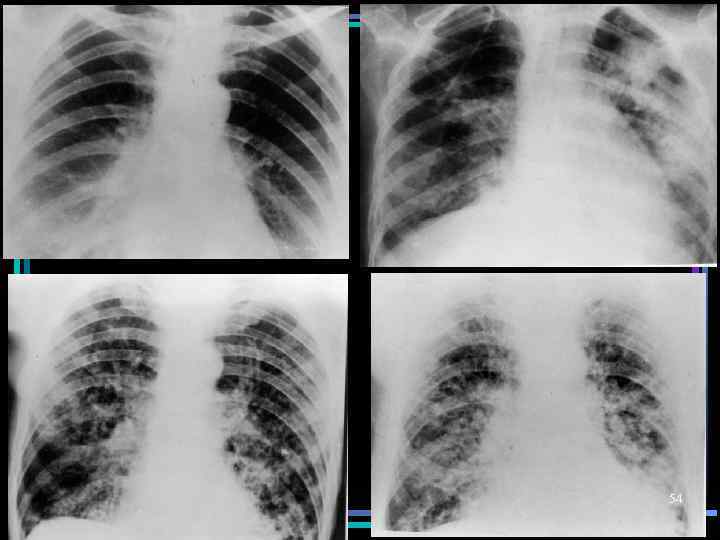

Клинико-морфологические стадии ОРДС • II стадия – экссудативная (2 -7 сутки) • Дефекты капиллярной стенки; • Скопление в интерстициальной ткани жидкости и фибрина; • Повреждение альвеолярной и базальной мембраны, пневмоцитов; • Нарушение системы сурфактанта; • Формирование гиалиновых мембран на стенках альвеол – грубые нарушения оксигенации • Рентген. изменения: усиление рисунка сосудов и бронхов, затемнение легочных полей (вплоть до облаковидных уплотнений), в тяжелых случаях – картина «белого легкого» 47

Клинико-морфологические стадии ОРДС • III стадия – пролиферативная (1 -4 нед) • Септальный, интерстициальный, внутриальвеолярный фиброз; • Избыточная пролиферация клеток • Присоединение воспалительного процесса • Рентген. изменения: просветление легочных полей, усиление сетчатополосатого рисунка, возможны очаги пневмонии. 48

54